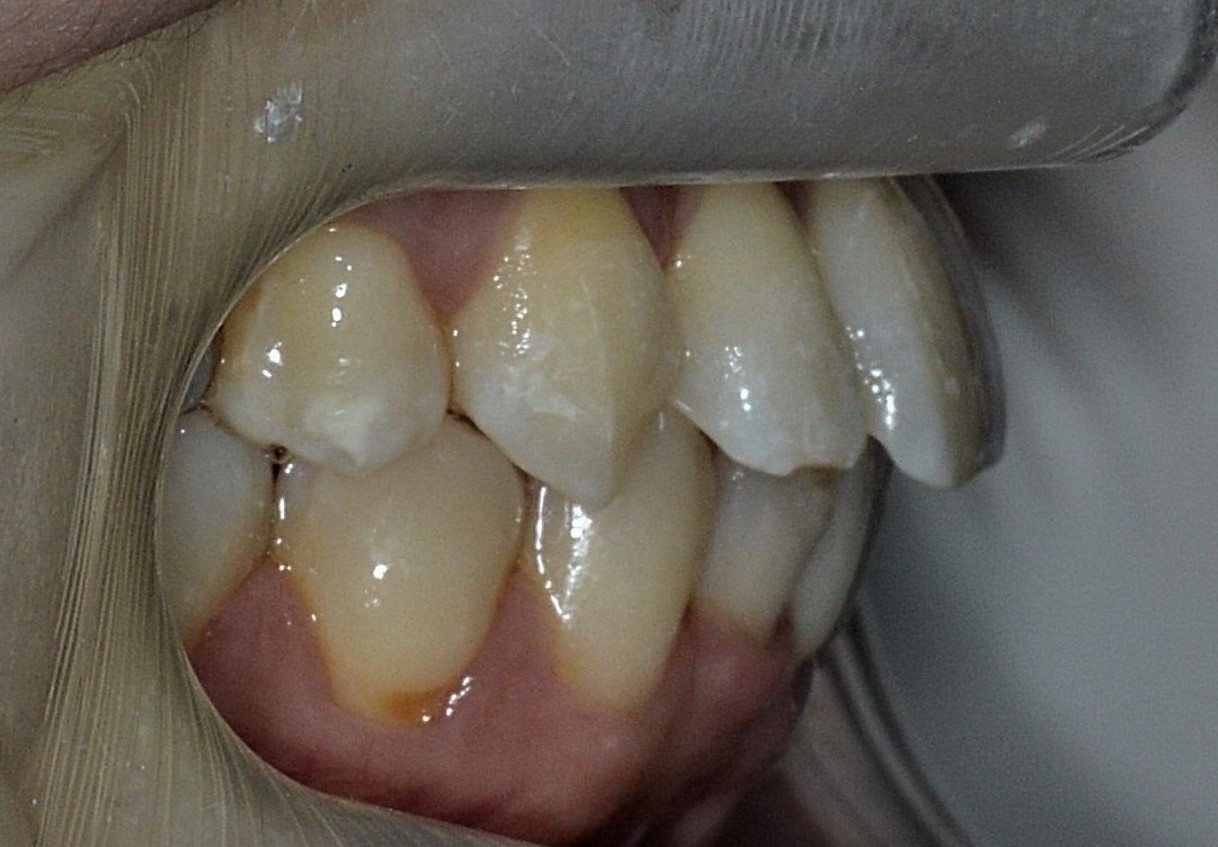

症例2

| 項目 | 詳細 |

|---|---|

| 患者様データ | 30代 女性 |

| 来院時の主訴 | 「右上の、内側に生えている歯が邪魔。」 |

| 矯正法 | 上の歯2本、下の歯2本、親知らず3本を抜歯しての矯正 |

| 通院期間 | 3年6ヶ月 |

| 治療費 | 総額:1,230,000円(税抜) 【内訳】 精密検査50,000円、メタルワイヤー矯正800,000円、月に1度の調整料5,000円、後戻り防止のリテーナー35,000円×2 |

| リスクと副作用 |

①歯を動かす事による痛みがあります。また、装置に慣れるまでは、口内炎ができやすいです。 ②歯肉が退縮するリスクがあります。装置が全ての歯に付くので、ハミガキが難しくなります。 ③長期的なメインテナンスが必要 |

| ここがこだわりのポイント!☝ | こちらの患者様は上の歯が1本内側に生えていましたが、奥歯の噛み合わせの方が問題でした。ハサミ状咬合といい、奥歯が極端に外側に向いており、下の歯と噛み合っていない状態でした。ハサミ状咬合は長期的にみると、前歯に大きな負担がかかったり、磨きにくい事による虫歯や歯周病になりやすいなどのリスクがあります。治療期間はかかりましたが、見た目の良さだけでなく、機能的にも改善しました。 |